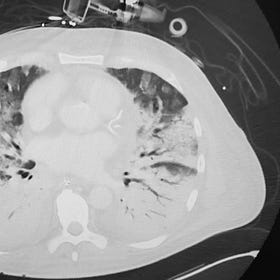

At a single tertiary cardiac bypass surgery center (Nanjing Drum Tower Hospital) in China, 424 patients were randomized to receive sivelistat or placebo within 6 hours of ICU admission in 2024-2025. Rigorous trial processes of randomization, blinding, and outcome measurement were described in the manuscript.

The authors report that sivelestat roughly halved the incidence of postoperative ARDS (16.8% vs 31.2%) and significantly reduced 90-day all-cause mortality (1.1% vs 5.2%), compared with placebo. There was no increase in mortality at 180 days.

Cases of ARDS in the sivelestat arm that did occur were milder, and there were no severe cases. Sivelistat-treated patients also had lower rates of adjudicated pneumonias and lower levels of numerous inflammatory markers. The results were published in JAMA Network Open in 2026.